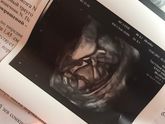

13 февраля 2017 17:41 Сходила я сегодня на внеплановое УЗИ ☺️ у нас будет сыночееек ❤️❤️ а я до последнего думала дочка, да и все думали ? Все с ним хорошо, открывал рот все время, потом уже растопырил ноги и мы с врачом увидели яйца и член ? Сказал только, что матка короткая … Читать далее